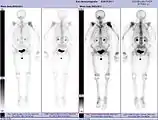

Scintigraphie corps entier avec 99mTc-HDP de la patiente avec une fracture du bras due à une métastase du cancer du sein